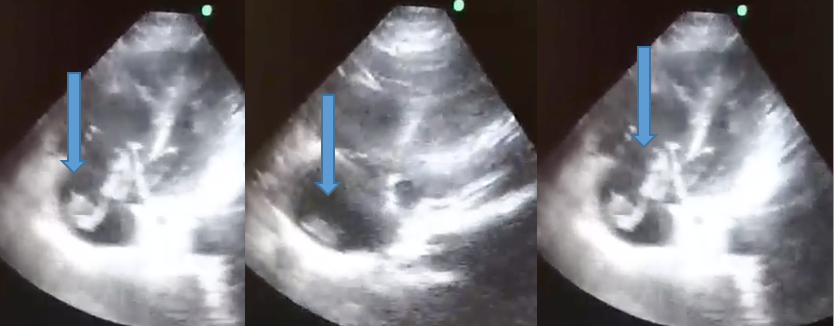

A detecção de um trombo em movimento na realização de um ecocardiograma é um evento raro. Relata-se o caso de uma paciente feminina, 66 anos, admitida com quadro de choque e submetida a realização de ultrassonografia à beira de leito, visualizando trombo saindo da veia cava para átrio direito e passando pela valva tricúspide até o ventrículo direito, direcionando com maior efetividade ao diagnostico e tratamento de tromboembolismo pulmonar. Demonstra-se a importância do conhecimento pratico e acessibilidade da ultrassonografia à beira de leito no atendimento de Emergência do Hospital Universitário Professor Polydoro Ernani de São Thiago.